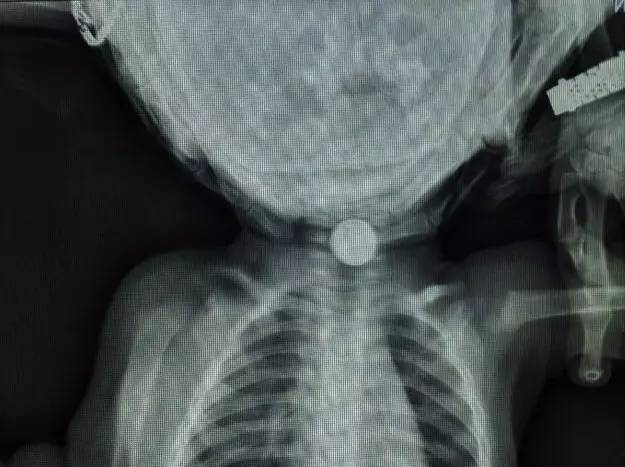

【可怕】泰州已有100多人吃了这些“奇珍异宝”,有的还差点丢了性命……医生表示很... |